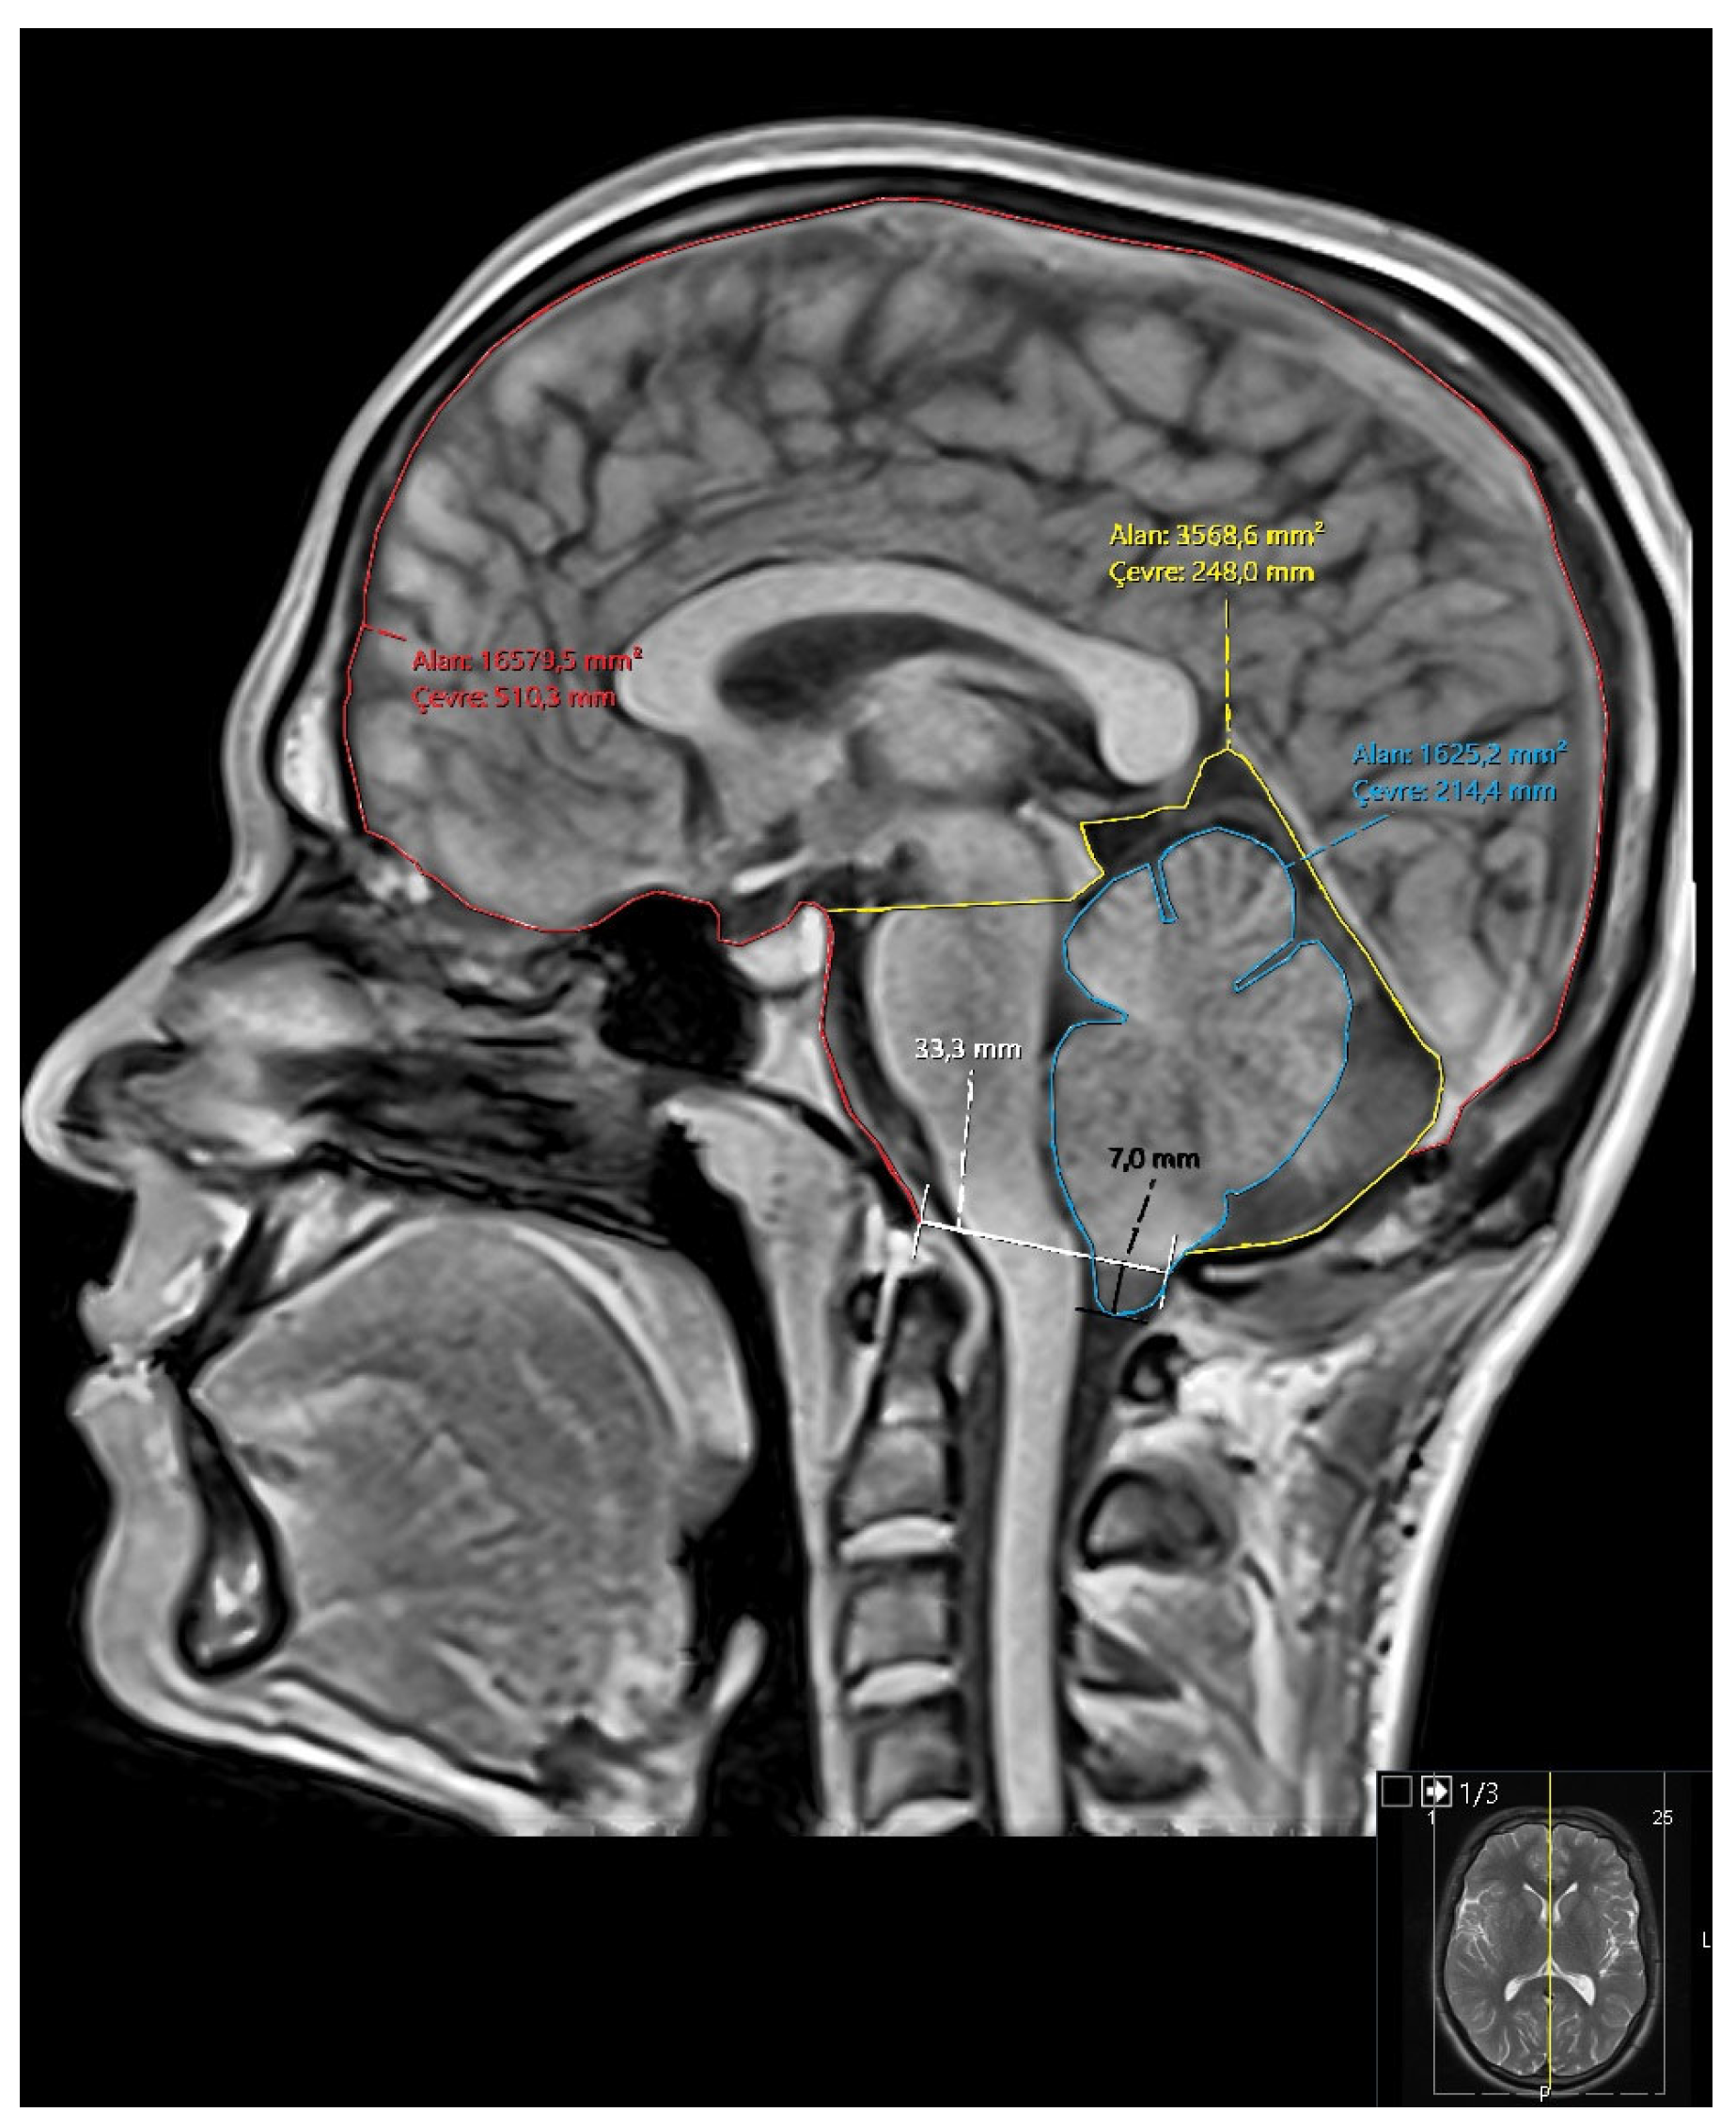

- Area and perimeter of the posterior fossa.

- Area and perimeter of the cerebellum.

- Area and perimeter of the intracranial cavity.

- Ratios: cerebellum/posterior fossa, posterior fossa/intracranial area, cerebellum/intracranial area (Figure 1).